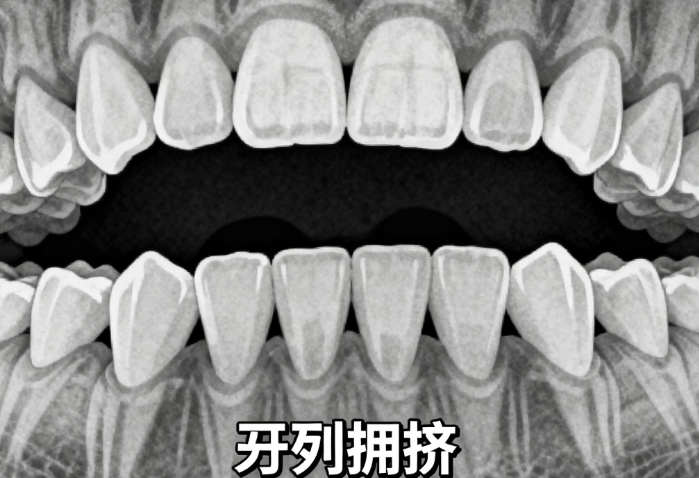

- 矫正难度:轻度牙列不齐(如个别牙拥挤)费用偏低,约8000-15000元;重度畸形(如较重龅牙、地包天需骨钉辅助)费用上涨,加骨钉需额外800-3000元/颗。